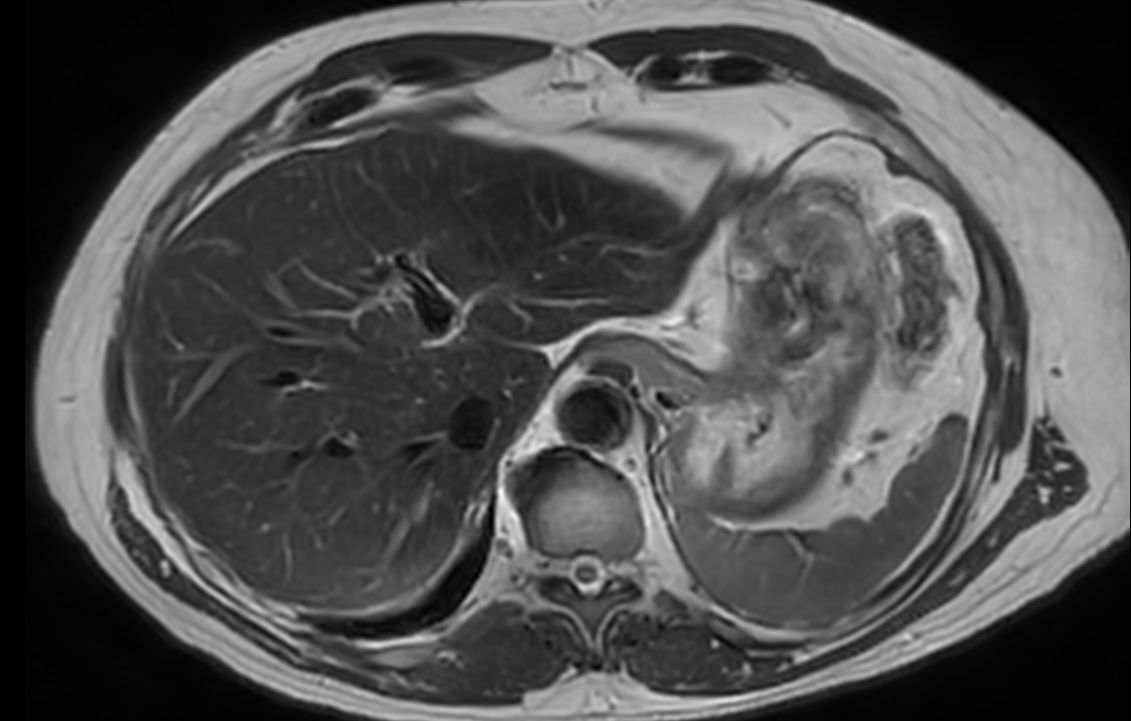

Axial T2w TSE mDIXON (water only)SmartSpeed MotionFree